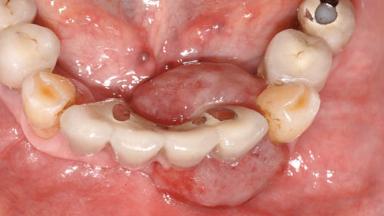

| Case Type | Extended Space |

|---|---|

| Jaw | Mandible |

| Area | Anterior|Posterior |

| # of Teeth | 10 |

| # of Implants | 5 |